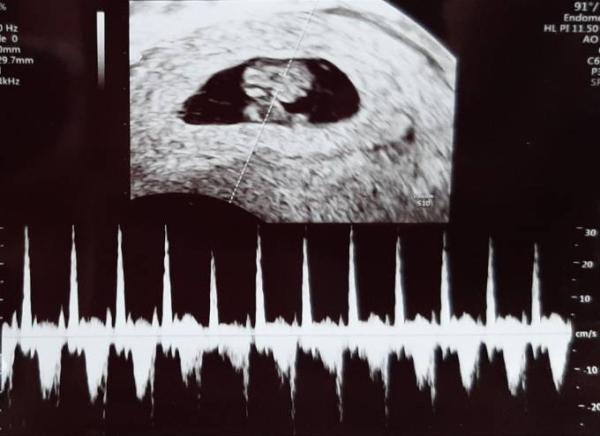

Hallo Mädels Ich war heute beim FA und mir wurde Blut entnommen, damit beim nächsten Termin der Mutterpass ausgestellt werden kann. War total aufgeregt, nach den letzten traurigen Tagen, wo viele ausgestiegen sind und sich Angst breit machte. Heute sah ich dann eine 1,1cm große dicke Bohne mit Herzschlag. Alles zeitgerecht entwickelt und der Wurm hat mein Herz gestohlen Ich wünsche allen Mitkugelnden weiterhin alles Gute, auch für eure Untermieter. Den Aussteigenden wünsche ich viel Kraft und alles Liebe für die Zukunft.

Bild zu Freude teilen - FA Termin😍 - Forum für Juli - Mamis